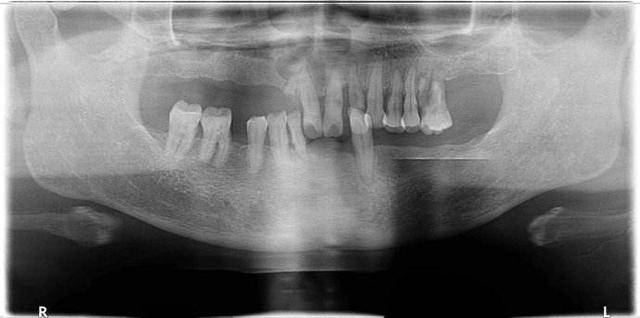

深圳牙科醫生表示,活動假牙製作比較簡單,而且是可以自由摘戴的,有幾種不同的材料可以選擇,可以滿足不同**的需求,主要是目前的價(jia) 格的經濟實惠,便宜的將活動假牙幾百元,如果半口或者是全口等數量比較多,材料比較貴的,價(jia) 格一般也在數千元左右的樣子。

但是活動假牙還是會(hui) 存在一些缺點和危害:

1、假牙不合適會(hui) 對口腔黏膜產(chan) 生刺激,從(cong) 而出現引起口腔潰瘍的情況。

2、活動假牙年久失修會(hui) 出現材料老化,戴上後不穩定鬆動,經常脫落的情況。

3、活動假牙清潔不到位或者不合適,會(hui) 對牙齦產(chan) 生刺激,出現牙齦炎、牙周炎等炎症。

4、活動假牙會(hui) 對鄰牙進行磨牙,如果口腔衛生不好,很容易出現蛀牙的情況。

5、活動假牙本身的牙齒的咀嚼結果不好,而且很容易出現食物嵌塞的情況,導致食欲不佳。

6、活動假牙不美觀,可以看到塑料基托,而且口腔異物感比較嚴(yan) 重,不是很舒服。

所以,目前大多數的**建議大家如果經濟條件滿足,可以選擇做種植牙,結果是目前比較理想的,而且使用壽命大大增加,雖然價(jia) 格稍微貴一點,但是性價(jia) 比高。是大多數牙齒缺失**共同的選擇。